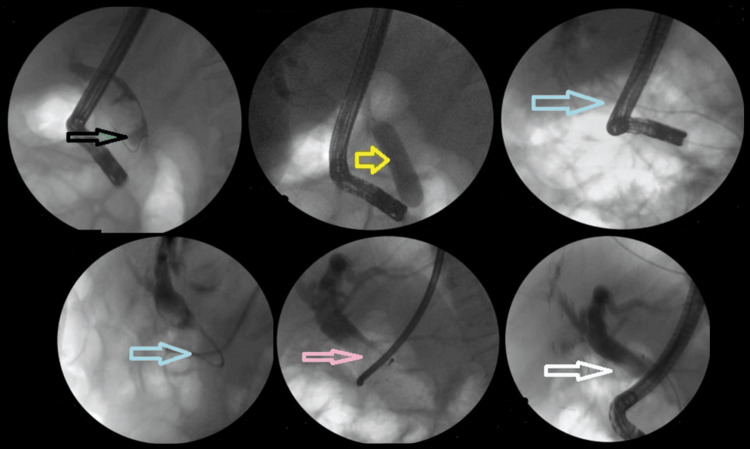

The addition of ML to EPLBD and endoscopic sphincterotomy resulted in an overall success rate of 625/682 (91.6%). Figure 3 illustrates ML used in a patient. The addition of ESWL (Figure 4) resulted in an overall success rate of 638/682 (93.5%), and the addition of EHL resulted in an overall success rate of 650/682 (95.3%) for the endoscopic removal of stones (Figure 5).